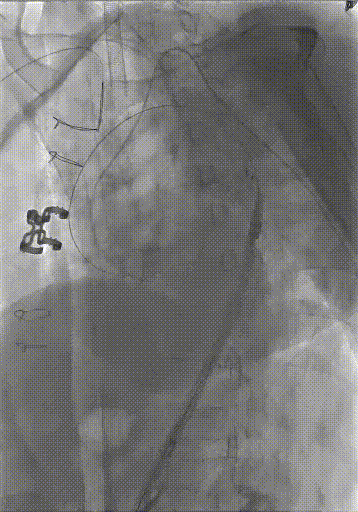

★ Case 3

男性,61岁,Bentall术后1年,主动脉弓部夹层;

既往史:高血压3级;

夹层动脉瘤CTA:A型主动脉夹层术后残余主动脉弓部夹层,头臂干及左颈总动脉根部夹层累及,向下累及胸腹主动脉至髂血管平面。

术前影像

造影后经股动脉导入并释放限制支架

经股动脉导入主体支架,抓捕无名动脉预留导丝,支架导入升主动脉

造影定位后释放主体支架

经股动脉依次超选导入分支支架,释放并球囊扩张,术毕造影

术后复查

三个穿刺点(双侧肱及单侧股动脉)无需颈部切口/穿刺

First In Man早期结果